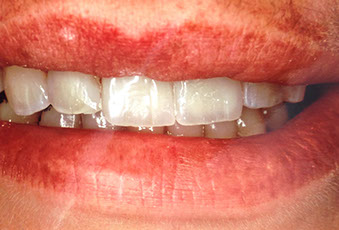

faccette estetiche

agenesia di un incisivo laterale